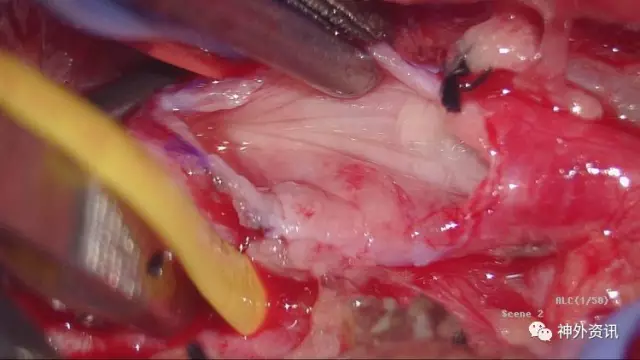

切开外中膜,先切开支架远端管腔,手术的关键是摘除支架,而远端血管通畅我们的手术会更有把握,刀尖切到之处有颅内反向血流溢出

切开外膜你看到了M,亮晶晶的金属支架嵌入增生内膜

支架马上就摘除了,成功在望

这是剥离支架后的外中膜

显微镜下7-0缝线缝合切口,松开阻断夹,VA管腔充盈好,无活动渗血,手术很顺利

这是切下的标本,切开后见支架被增生内膜包裹,内腔消失